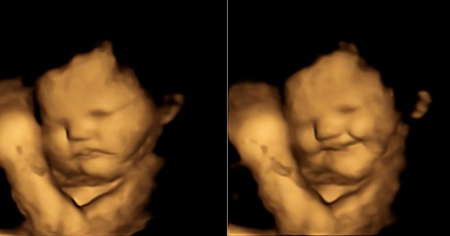

Se gli piace ciò che mangia la madre, sorridono. Se non gli piace, piangono.

I risultati della ricerca guidata da Beyza Nur Ustun sono stati condotti mediante la tecnica dell'ecografia 4D, con la quale è stato possibile osservare per la prima volta come i nascituri reagiscano agli stimoli gustativi. Chiaramente, questo accade perché accolgono ciò che la madre mangia attraverso il liquido amniotico.

Per lo studio, pubblicato sulla rivista Psychological Science, la psicologa e il suo team hanno preso in esame le immagini ecografiche 4D di 100 donne incinte (a 32 e 36 settimane di gravidanza) che avevano assunto delle capsule di carota o di cavolo riccio, a stomaco vuoto.

L'analisi delle registrazioni ha mostrato che i feti esposti al gusto dolce della carota mostravano una sorta di sorriso, mentre quelli esposti al gusto amarognolo del cavolo riccio contorcevano il viso come se stessero piangendo. «Siamo stati in grado di rilevare le reazioni facciali nei feti già 30 minuti dopo che le madri avevano ingerito le capsule aromatiche», scrivono Ustun e i suoi colleghi. «È stato davvero incredibile vedere le reazioni dei bambini all'aroma di carota o di cavolo piuma e condividere questo momento con le loro madri».